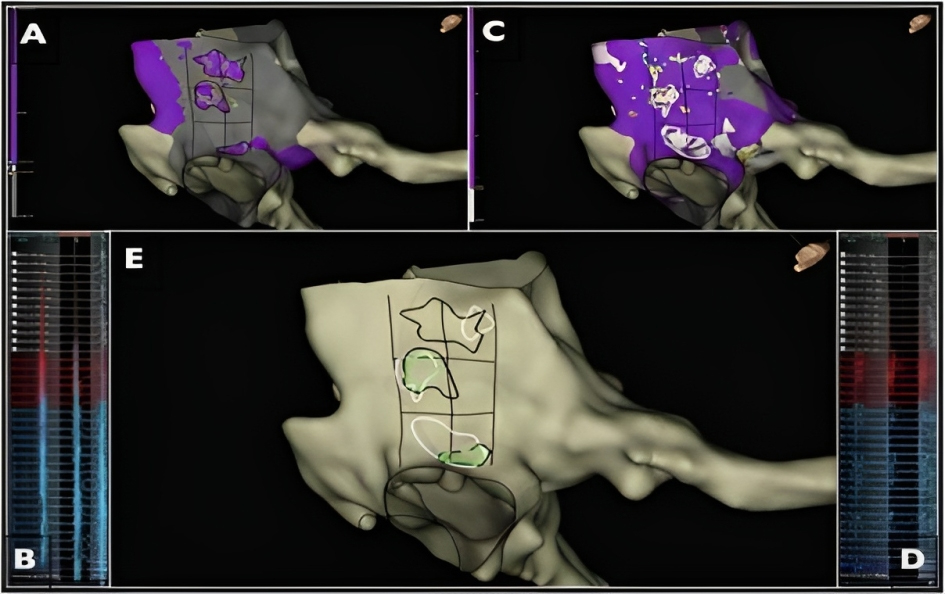

(d) Point applications directed by wavefront speed and maximum voltage criteria (omnipolar mapping). Omnipolar mapping [139] is a new technology available in EnSite X™ EP System (Abbott, Abbott Park, IL, USA) with the Advisor™ HD Grid (HDG) mapping catheter (Abbott), in which signals are calculated from cliques, composed of 3 unipoles and 2 orthogonal bipoles. Omnipolar electrograms provide a local signal, like a bipolar electrogram (EGM), with instantaneous information on the direction and speed of the wavefront, like a unipolar EGM, and they are displayed as beat-by-beat activation vectors. Maximum voltage can also be determined because it is truly independent of catheter–wavefront orientation. Recently, Vallès et al. [140] have shown that slow CTI conduction pathways can be identified by omnipolar vectors, representing unique conduction corridors in the CTI. These areas are surrounded by large muscle fibers, which are often detected on omnipolar mapping as high voltage areas (Fig. 12, Ref. [140]). Ablation in areas of slow conduction would achieve CTI bidirectional block in more than 92% of patients, suggesting they should be targeted preferentially. Possible advantages of this approach could include less procedure and fluoroscopy time, and a reduction in RF burden.

Fig. 12.Radiofrequency applications directed by wavefront speed and maximum voltage criteria (omnipolar mapping). Images from Vallés et al. [140] obtained by using the EnSite X mapping system and omnipolar technique showing the CTI in LAO caudal view. (A) Representation of high voltage areas, encircled in black. (B) Large electrograms in those high voltage areas. (C) Areas of slow wave speed, encircled in white. (D) Displays the fractionated EGMs in those low wave speed areas. (E) All the previous areas are displayed, highlighting confluent sites encircled in green. LAO, left anterior oblique; CTI, cavotricuspid isthmus.